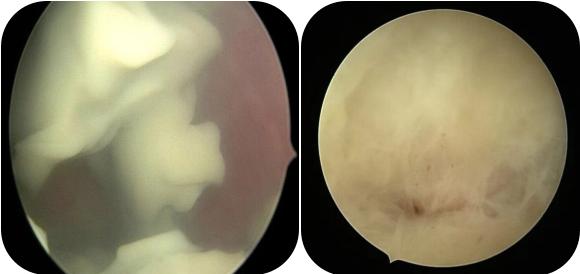

宫腔镜直视下观察宫腔,一般可见宫腔内有淡黄色或黄色脓液,伴或不伴内壁黄白色脓苔组织。宫腔镜检查需要充分引流,在急性炎症控制后进行。子宫穿孔或急性感染期子宫较大、宫壁较薄为宫腔镜检查的禁忌证。应充分引流脓液后谨慎操作,低压膨宫以免导致医源性子宫破裂。

5.宫腔镜治疗:宫腔镜可直视评估宫腔并活检,可冲洗引流黏稠脓液,提高诊治安全性,降低穿孔风险。